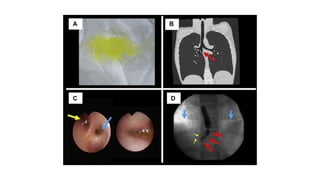

•A well-defined oval shaped large intra-pleural cystic lesion with numerous daughter cysts

inside is seen in the left side of the chest. It showed fluid CT density, smooth margin,

hypodense content relative to the capsule with a thin enhancing capsule, picture highly in

favor of an uncomplicated pleural hydatid cyst.

Both lungs clear with normal pulmonary vascular markings, no focal lesion.

Normal mediastinum with normal mediastinal vasculature, no mass or enlarged LN.

• Axial C+ arterial phase

Axial lung window

• Coronal

• The patient underwent

thoracotomy and the

findings of numerous

cystic lesions within

the pleura confirming

the diagnosis of

hydatid cysts.